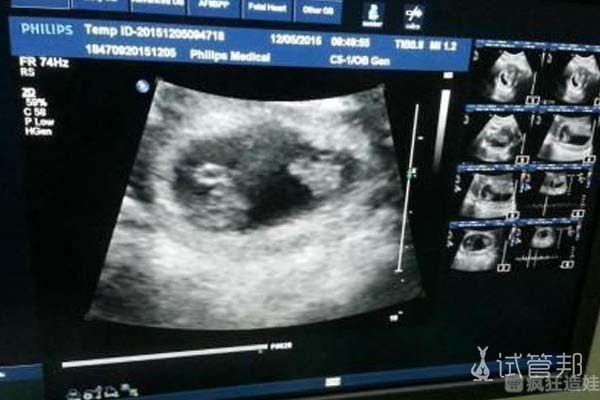

检查结果出来之后,发现是我的问题,我不仅有卵巢囊肿,而且双侧输卵管堵塞。怀孕的几率非常小。医生说的时候,我感到很震惊,而且整个人感觉都不好了。但幸运的是,我丈夫的精液是正常的。医生说把我的问题解决了怀孕的几率就很大了。医生建议我们做二代试管婴儿。我想了想,最终同意了。没想到这才是我崩溃的开端。

为了解决这些问题,我做了微创手术,肚子上打了几个洞。手术后医生说囊肿是良性的,输卵管也疏通了。我当时本来很开心,想着马上就可以怀孕了。医生让我我回去休息几个月,休息过后就可以开启试管流程了。我看来很多资料,也积极备孕。在网上买了排卵试纸,温度计,开始每天测体温、测试排卵情况。医生通知我后,我立刻就去医院打针促排卵了。但让我很难受的是,第一次取卵很失败,培养出来的胚胎质量也很差。第一次二代试管婴儿就这么失败了。